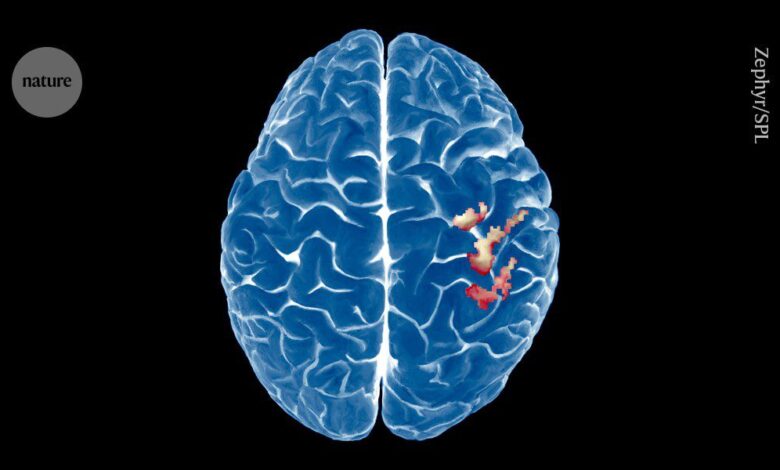

خريطة الدماغ للجسم مستقرة بشكل مدهش – حتى بعد فقد الطرف

خريطة الدماغ للجسم في القشرة الحسية الجسدية الأولية لا تزال دون تغيير بعد البتر.الائتمان: Zephyr/Science Photo Library

لقد رفعت دراسة تصوير الدماغ للأشخاص ذوي الأسلحة المبتورة اعتقادًا طويلًا: أن خريطة الدماغ للجسم تعيد تنظيم نفسها للتعويض عن أجزاء الجسم المفقودة.

لكن أحدث النتائج ، نشرت في علم الأعصاب الطبيعة في 21 أغسطس2، تكشف أن القشرة الحسية الجسدية الأولية تظل ثابتة بشكل ملحوظ حتى بعد سنوات من بتر الذراع. يقول المؤلفون إن الدراسة تدحض المعرفة التأسيسية في مجال علم الأعصاب أن فقدان الطرف يؤدي إلى إعادة تنظيم جذري لهذه المنطقة.

وكشف التحليل أن تمثيل الدماغ للجسم كان متسقًا بعد بتر الذراع. حتى بعد خمس سنوات من الجراحة ، كانت الخريطة القشرية لليد المفقودة لا تزال يتم تنشيطها بنفس الطريقة التي كانت قبل البتر. لم يكن هناك أيضًا دليل على أن التمثيل القشري للشفاه قد تحول إلى منطقة اليد بعد البتر – وهو ما ستحدث الدراسات السابقة.

يقول ماكين إن دراستهم هي “الدليل المباشر الأكثر حاسماً” على أن خريطة الجسم التي تم إنشاؤها في الدماغ لا تزال مستقرة بعد فقدان الطرف. وتقول: “إنه يتعارض مع المعرفة التأسيسية للحقل”.